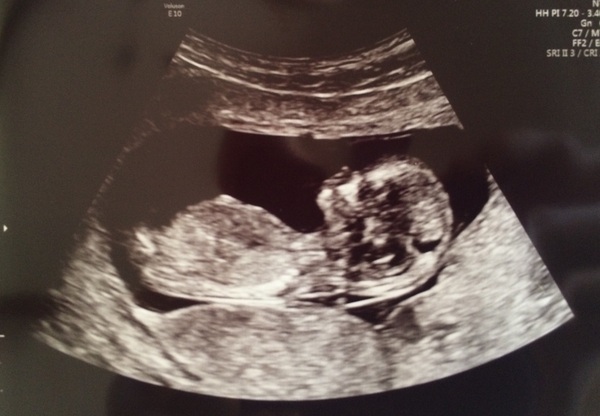

Great scan picture blondes.

Had a rubbish day here, nausea was back on and off, think it was from being out too much with the scan and running round after DS etc. On the bright side, baby is totally fine, very wriggly and not at all affected by the cocktail of pills I'm taking every other hour of the day! Looks very chilled out in this pic though.

Lovely scan pictures Captain and Blondes and so glad to hear you are doing better peace!

CaptanWarbeck That's a nice scan picture. Glad all went well.

Lovely scan of BabyCaptain 😊